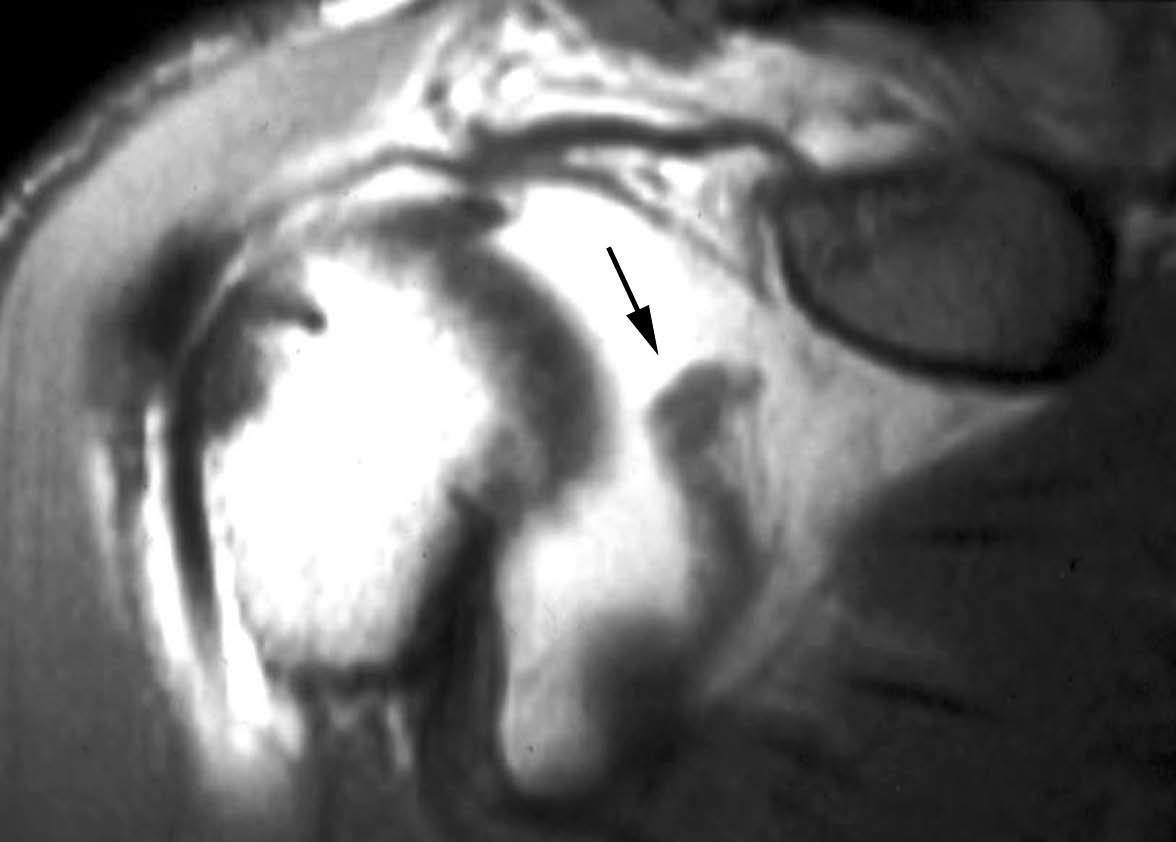

Lesión de Perthes

La lesión de Perthes es similar a la de Bankart, con la excepción de que no existe rotura capsuloperióstica, aunque el periostio puede estar separado del borde anterior del margen glenoideo (fig. 10). Esta lesión puede ser difícil de visualizar, incluso con artrorresonancia, a menos que se obtengan imágenes con la posición de abducción y rotación externa (ABER). En un estudio de 10 casos, verificados quirúrgicamente, Wisher et al17 comprobaron que el 50% de las lesiones de Perthes sólo podían visualizarse en la posición de ABER.

Fig. 10.--Lesión de Perthes. Artrorresonancia T1 con saturación grasa en posición ABER (abducción y rotación externa), donde se observa un arrancamiento parcial del labio glenoideo (flecha) con conservación de la unión capsuloperióstica.